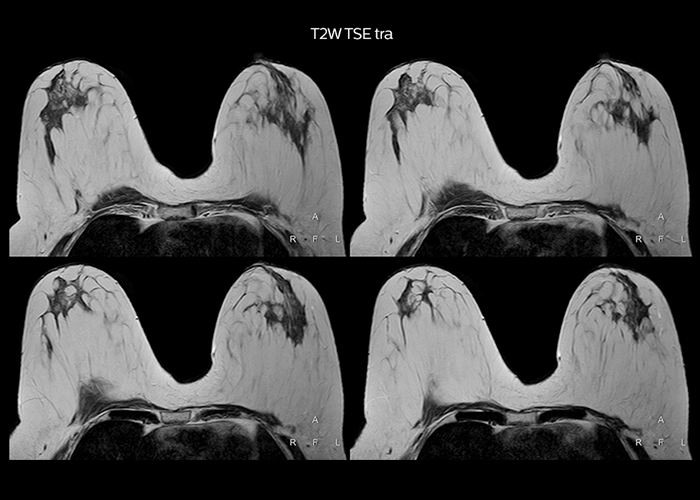

“On average, we scan about 80 patients per day, but on some days we scan well over 100 patients. The scanner is in use 7 days per week, operated 20 hours per day on week days and 8 hours per day in the weekend,” Mr. Tuna says. “To avoid coil changes we plan examinations of similar anatomies back to back, such as head and spine. Multiva helps us here a lot because coils don’t need to be changed frequently. Moreover, thanks to parallel imaging technology and 16-channel HeadSpineTorso and 8-channel MSK coils we are able to achieve excellent image quality. In this way Multiva helped us to increase both image quality and productivity.” “Neurological cases, such as brain and spine imaging, represent the largest share in our MR scanning, followed by musculoskeletal cases. In general, we use simple and basic imaging protocols. But occasionally, we use advanced techniques for problematic cases if necessary.

“Since we have Multiva, we have improved our workflow, because it has been so easy for our operators to learn and use Multiva. Our operators notice that the coils are lightweight and coils don’t need to be changed frequently. The user interface is easy to use. Features like this help us to scan a high number of patients. For instance, the musculoskeletal coils can be used interchangeably, and due to the user-friendly interface, the number of mistakes such as, for example, correct coil element selection has decreased significantly, because the system does it automatically by itself.” “Most important, Multiva satisfies our clinical imaging needs very well,” says Mr. Tuna. “Many features of Multiva have become similar to the Ingenia system. Even in more complex imaging such as abdominal and cardiac, the image quality and performance of Multiva is better than we expected. General surgeons and physicians from our hospital’s internal medicine department prefer to refer to us because of this.”

“Overall, Multiva provides what we need in term of patient needs and even potential needs,” says Mr. Tuna. “It allows us to scan a high patient volume and image a large variety of anatomies and conditions.” “Our goal is to achieve uncompromising quality based on universal standards, while solving clinically complex cases. Our Multiva scanner allows high productivity with fast imaging time, and allows us to make confident diagnoses in a broad range of cases.” “It’s an excellent multi-purpose scanner that satisfies all our MR imaging requirements in the hospital,” he concludes.